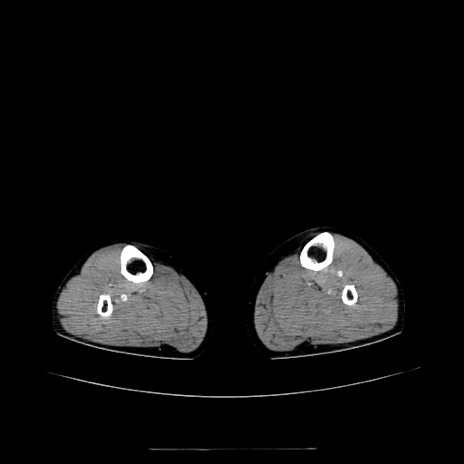

症例5(横断像)

【症例】70歳代女性

【主訴】お腹が張る

【現病歴】1週間くらい前から腹部膨満の自覚あり。昨日夜から増悪したため、本日救急外来受診。

【身体所見】意識清明、BT 36.5℃、BP 165/106mmHg、HR 80bpm、SpO2 98%、腹部:膨満、軟、自発痛・圧痛なし、触診にて不快感あり、腸蠕動音:減弱

【データ】WBC 12600、CRP 1.04